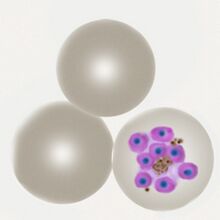

The gametocyte

The sexual replication in P.falciparum is very distinctive and may be the only form visible (particularly of after treatment).

- male and femaie gametocytes have the appearance of rods although these may be distorted

- The rod shapes may become curved by the red cell membrane to give the characteristic "banana" form”

- The residual membrane (empty of haemoglobin) is often seen as a "blister" to one or both sides of the parasite

- The single chromatin area is in the centre of the parasite, often has pigment overlying it

P.falciparum gametocytes